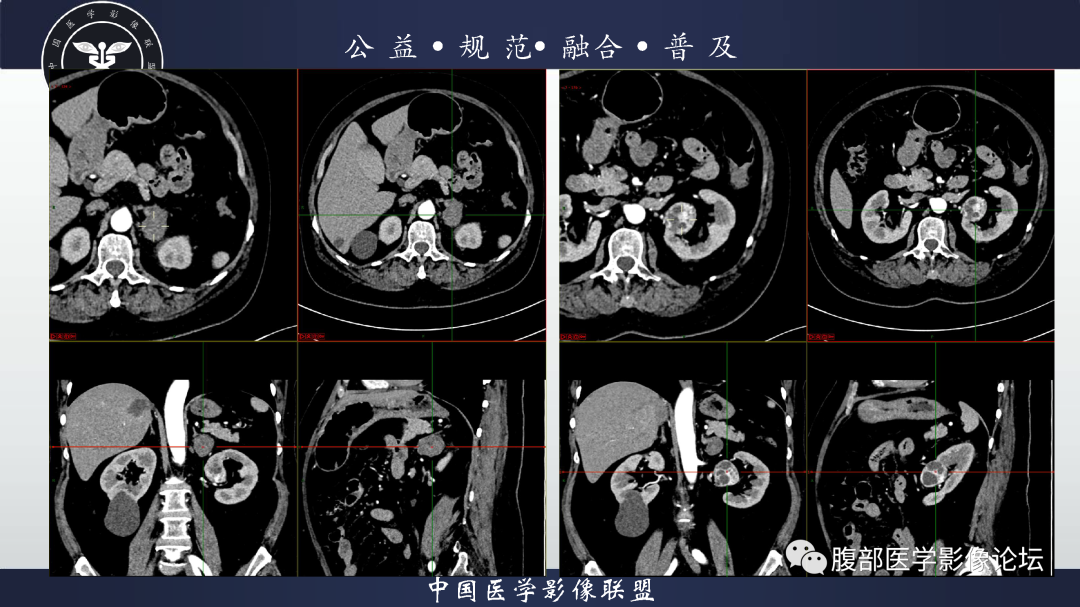

【病例】肾脏透明细胞癌1例CT影像-4